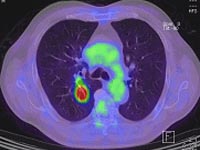

赤穂中央病院での肺がん治療の特徴は診断から手術や化学療法などの治療を一貫して呼吸器科で行うことにある。また、胸腔鏡手術や肺を残す縮小手術を行っていること、PET検査を活用していることも挙げられる。診断法にあたっても、PET検査のみならず、気管支鏡やベテランの放射線科医によるCTガイド肺生検、胸腔鏡生検などを駆使し、正確な診断をつけている。